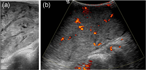

Diffuse vascular malformation of large intestine clinically and radiologically misdiagnosed as ulcerative colitis

Dilasma Ghartimagar and others

Journal of Surgical Case Reports, Volume 2017, Issue 2, February 2017, rjx016, https://doi.org/10.1093/jscr/rjx016